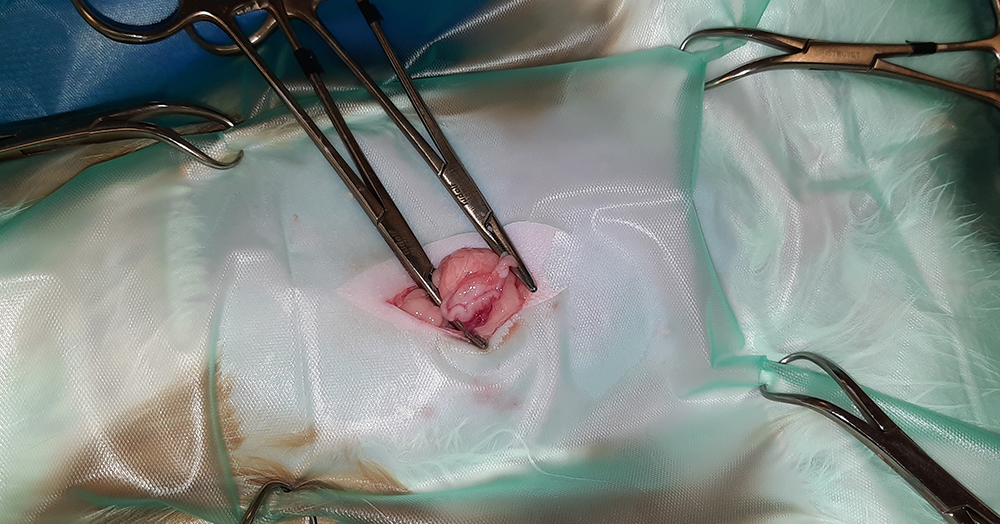

Er wordt een kleine snede gemaakt in de buik, ter hoogte van de navel. Vervolgens worden na elkaar de twee ovaria (=eierstokken) opgezocht, de aanvoerende bloedvaten afgebonden en de eierstokken verwijderd. Hierna wordt de buik in 3 lagen gesloten; de spierlaag, de onderhuid en de huid. Deze laatste wordt onderhuids gesloten met soms een enkele uitwendige knoophechting, zodat er zo min mogelijk hechtingen zichtbaar zijn. Er wordt een wondpleister geplaatst, nadat het wondgebied voorzichtig is schoongemaakt.